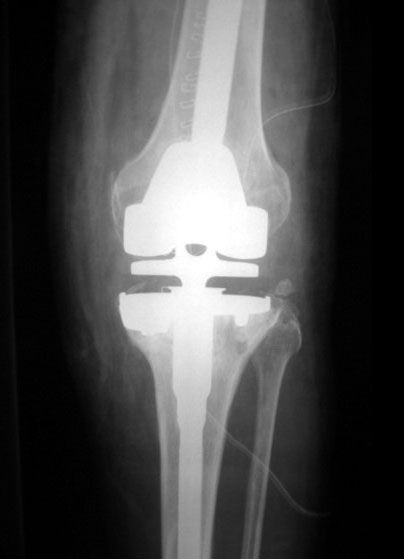

Failed TKR

Revised TKR